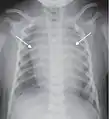

![]() A normal posteroanterior (PA) chest radiograph of someone with Interstitial Pneumonia. Dx and Sin stand for "right" and "left" respectively. | |